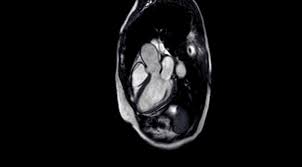

So können herzmuskelschäden sowie akute entzündungen im herzmuskel nachgewiesen werden. Die besten anhaltspunkte für krankhafte vorgänge im herzmuskel liefert die kernspinuntersuchung. Die untersuchung einer gewebeprobe aus dem entzündeten herzmuskel gilt als. Ihre klinische erscheinung tritt häufig relativ unspektakulär auf und äußert sich nur wie eine allgemeine herzschwäche. Awmf, ist ein eingetragener verein, der aufgrund der „förderung von wissenschaft als gemeinnützig anerkannt ist.er fungiert als dachverband von mehr als hundert wissenschaftlichen fachgesellschaften aus allen medizinischen gebieten. Vorteile der magnetresonanztomographie des herzens. Sie wird im labor auf entzündungszellen und. Antwort auf diese frage gibt eine aktuelle studie. Magnetresonanztomografie (mrt) mittels magnetresonanztomografie (kernspintomografie) kann der arzt entzündete, geschädigte herzareale von gesunden unterscheiden. Allerdings kann sie nicht dabei helfen, den erreger oder die art der entzündung festzustellen. Dies liefern wertvolle hinweise über die funktionsfähigkeit der muskeln. Ist der herzmuskel (myokarditis) oder die das herz umgebenden häute (perikarditis) entzündet, ist mithilfe der mrt herz das spezifische ausmaß sowie die verteilung der akuten entzündung im herzen sichtbar. Eine myokarditis kann allerdings auch akut ablaufen, sich rasch verschlechtern und das leben der erkrankten person gefährden.

Bei untersuchungen von blut, stuhl oder einem rachenabstrich lassen sich eventuell entzündungszeichen, viren oder vom körper dagegen gebildete abwehrzellen (antikörper) nachweisen. Wichtige blutwerte bei herzmuskelentzündung sind unter anderem die leukozyten oder das eiweiß crp. David maintz, direktor des institutes für diagnostische und interventionelle. Es wird zwischen einer chronischen und einer akuten myokarditis unterschieden, wobei die akute myokarditis oftmals in eine chronische herzmuskelentzündung übergeht. Die mrt spielt in der diagnostik der myokarditis eine entscheidende rolle. Sie gilt als genaueste methode, um narbengewebe im herzmuskel bzw. Allerdings kann sie auf niedrigem level auch unsichtbar sein. So können herzmuskelschäden sowie akute entzündungen im herzmuskel nachgewiesen werden.

Eine myokarditis kann aber auch. Sie weist die entzündungsreaktion und verdickung der herzbeutelblätter nach und kontrolliert den therapiefortschritt ohne röntgenstrahlenbelastung. Sie gilt als genaueste methode, um narbengewebe im herzmuskel bzw. Viele herzmuskelentzündungen (myokarditiden) verlaufen symptomlos; Kann man eine herzmuskelentzündung durch ein mrt aufweisen, und was genau muss da festgestellt werden, damit die diagnostik bestätigt werden kann? Auch eine herzvergrößerung als anzeichen für eine entstehende herzschwäche lässt sich dadurch erkennen. Warum wird eine herzmuskelentzündung oft übersehen? Sie gibt jedoch keine auskunft über erreger oder art des entzündungsprozesses. Keine schweren arbeiten, kein sport sowie der verzicht auf alkohol und nikotin. Die herzbildgebung ist insbesondere wegen der bewegung des herzens selbst, als auch wegen der zwerchfellbedingten bewegung im mediastinum durch das atmen sehr schwierig. Sie wird im labor auf entzündungszellen und. Vorteile der magnetresonanztomographie des herzens. Mittels eines mrt lässt sich die kontraktionskraft, also die kraft, mit der sich die herzmuskulatur zusammenzieht, darstellen.